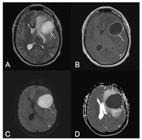

Neurological manifestations occur in 1–5% of patients with dengue, affecting the central nervous system in rare cases